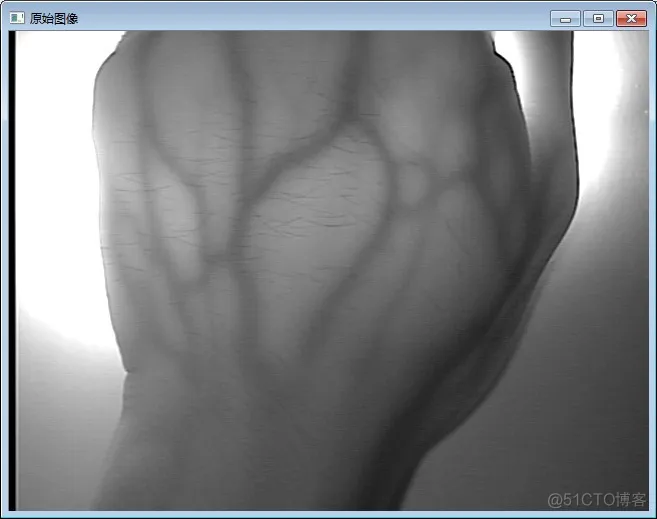

🌸CLAHE算法的应用:对于医学图像,特别是医学红外图像的增强效果非常明显:这篇博客做出了非常详细的讲解👉🏻CLAHE的实现和研究

这里放两张出自这篇博客的对比图感受一下: